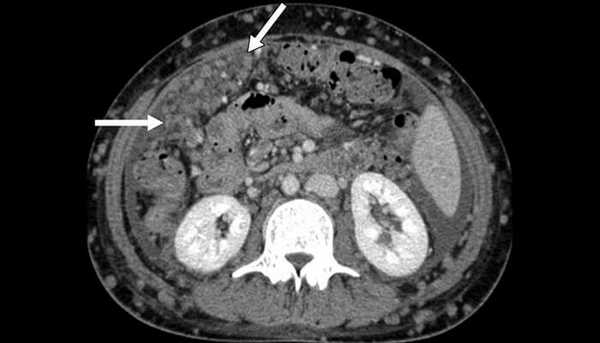

Канцероматоз брюшины

Злокачественные клетки, попадающие в брюшную полость, быстро распространяются по брюшине и образуют множественные мелкие очаги. На момент постановки диагноза «рак желудка» канцероматоз брюшины выявляется у 30-40% пациентов. При раке яичников вторичные опухоли брюшины обнаруживаются у 70% больных. Патология сопровождается появлением обильного выпота в брюшной полости. Больные истощены, выявляются слабость, утомляемость, нарушения стула, тошнота и рвота. Крупные опухоли брюшины могут пальпироваться через брюшную стенку.

Различают три степени канцероматоза: локальный (выявляется одна зона поражения), с поражением нескольких участков (очаги поражения чередуются с зонами неизмененной брюшины) и распространенный (обнаруживаются множественные вторичные опухоли брюшины). При недиагностированной первичной опухоли и множественных узлах брюшины клиническая диагностика в ряде случаев представляет затруднения из-за сходства с картиной туберкулезного перитонита. В пользу вторичных опухолей брюшины свидетельствует геморрагический характер выпота и быстрое повторное возникновение асцита после проведения лапароцентеза.

Диагноз устанавливается с учетом анамнеза, клинических проявлений, данных УЗИ органов брюшной полости, МСКТ брюшной полости с контрастированием, цитология асцитической жидкости, полученной при проведении лапароцентеза, и гистологического исследования образца ткани опухоли брюшины, взятого в ходе лапароскопии. В качестве дополнительной диагностической методики может применяться тест на онкомаркеры, позволяющий более точно определять прогноз, своевременно выявлять рецидивы и оценивать эффективность терапии.

Канцероматоз брюшины, компьютерная томография